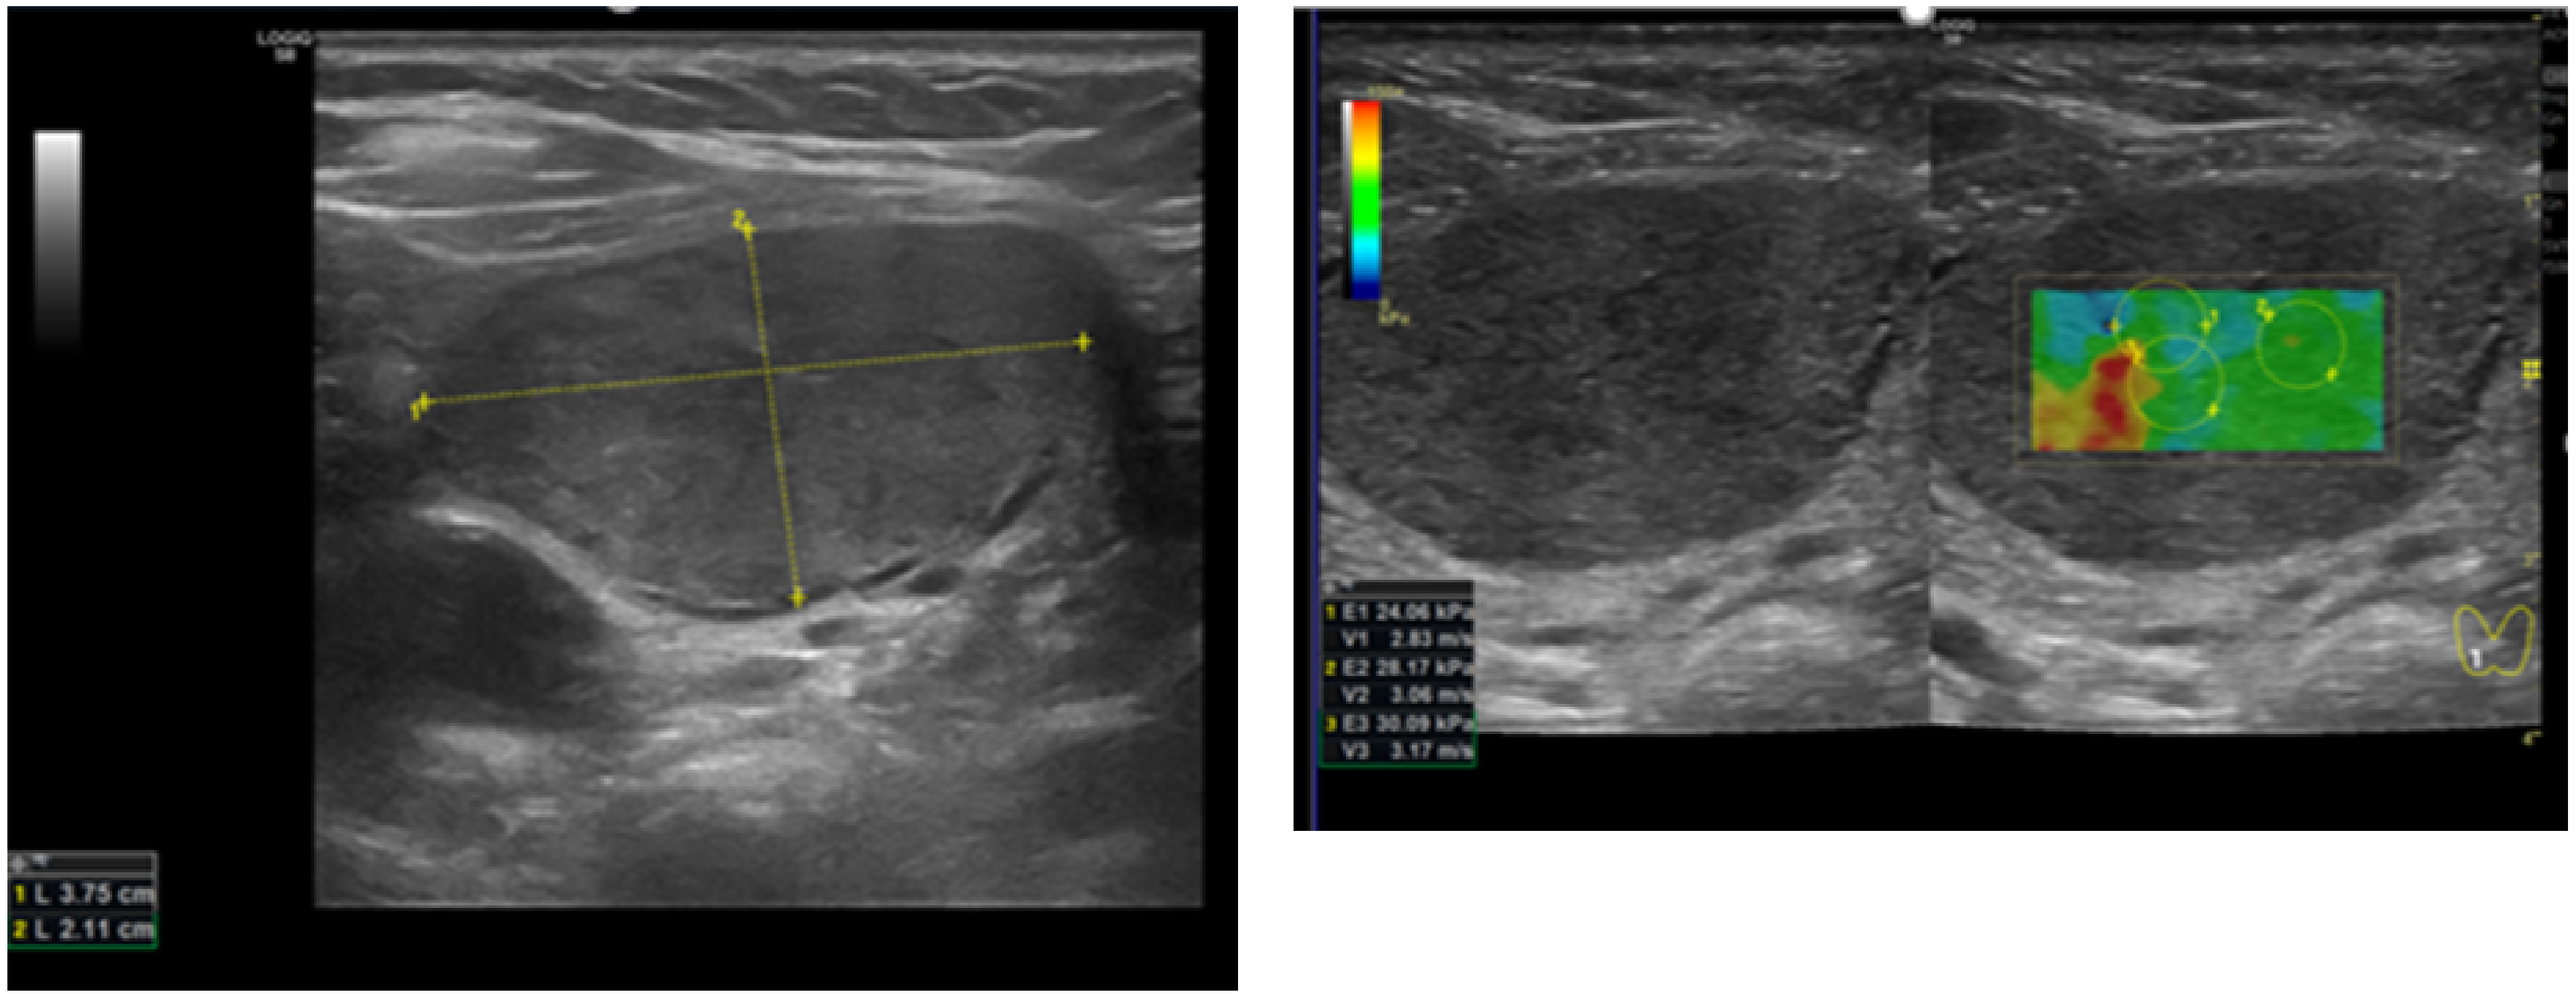

2.2. Thyroid US and SWE